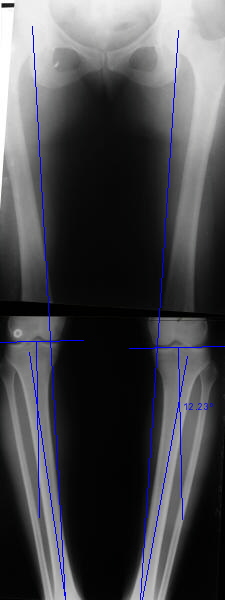

Отправитель: T. Derek V. Cooke 13 Сентябрь 2005, 23:51

|

Hello Alex:

Thanks for the clinical photo.

Your patient appears to have "Insquinting Knees"?

I am attaching a word doc with a 'print screen' of the program in use, showing the images being viewed and analysed

. On the right leg you can see some of the tools (from the tool bar above) applied to demonstrate a mild mech-axis varus of about 5 degrees.

On the left the bone landmarks used in the anlaysis are shown.

The data for the analysis are in the XLs sheet below, exported from the program automatically.

I have given a label of the abreviations and some normative values.

In essence she has a mild mech-axis varus of 7 degrees with some contribution from the femur (2) degrees and more from the tibia (6 degrees), none from the joint.

The analysis took about 6 mins.

Regards

Derek

TDVC> In essence she has a mild mech-axis varus of 7 degrees

TDVC> with some contribution from the femur (2) degrees and more from

TDVC> the tibia (6 degrees), none from the joint.

And what is conclusion? Should it be corrected, by what means, at what level, to what axis, with what lateral/medial translation?